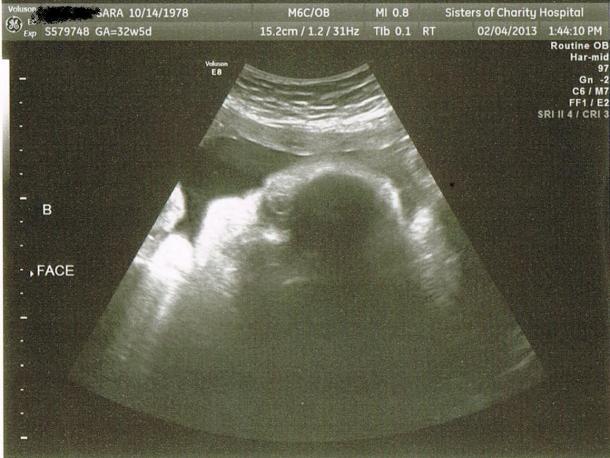

Yesterday was my 32-week ultrasound, and I cannot even believe how much bigger the babies are after just 4 weeks. The ultrasound tech struggled to get good measurements because there is just so much baby filling me up. Sadly, Miss Molly is still breach and her head is sort of locked under Gus’s feet. He has long legs that are wedged way up under my ribs, and is more transverse than head down. It looks like we are without a doubt headed to c-section city. The babies weigh in at 4lba12oz (Molly) and 5lbs (Gus). We are still under Eddie’s total birth weight, but you have to figure with fluid and placentas, not to mention that they are 2 separate people, that I have never in my life been as pregnant as I am now. We did get some decent baby face shots. Gus (Baby B) makes me just want to shout “CHEEEEKS!” They were so prominent that I pointed them out on the screen.

And here’s Gus:

It’s maybe harder to tell from the scanned version, but I can totally see their little faces. Real live babies, you guys!